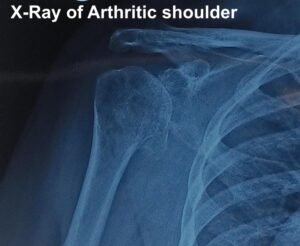

What are the investigations needed?

X-ray of the shoulder joint is needed to confirm the presence of arthritis. They can also be used to grade the severity of arthritis.